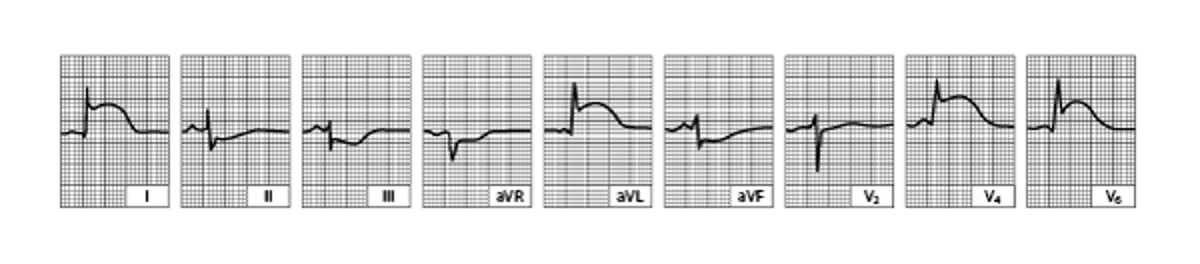

Acute Lateral Left Ventricular Infarction (tracing obtained within a few hours of onset of illness)

There is striking hyperacute ST-segment elevation in leads I, aVL, V4, and V6 and reciprocal depression in other leads.